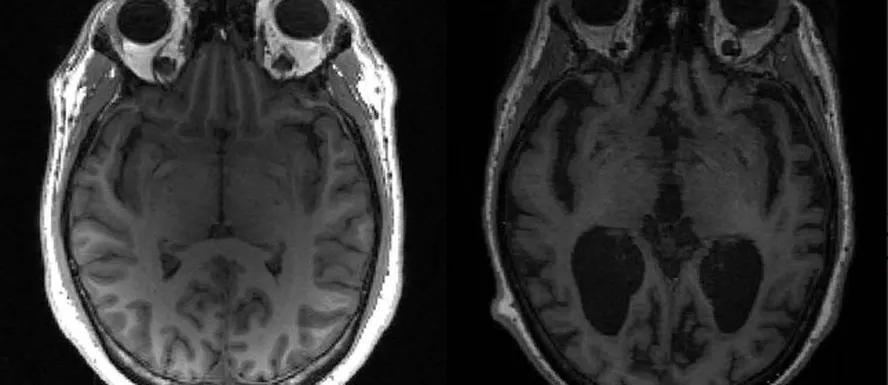

Legenda: Cérebro saudável aparece à esquerda e cérebro com Alzheimer à direita, evidenciando as diferenças

Foto: Reprodução